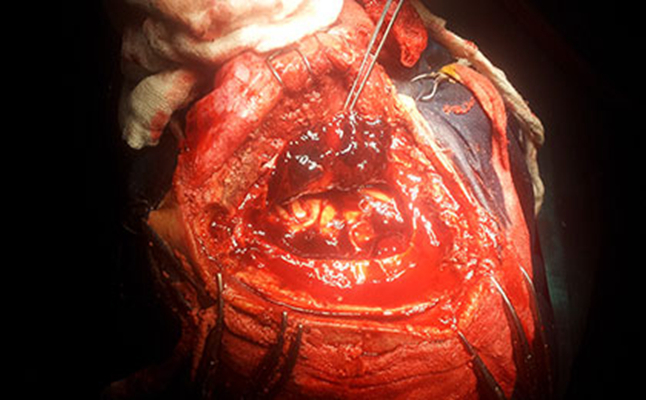

顱內血腫圖片

硬膜下血腫 (48)

硬膜下血腫 (49)

硬膜下血腫 (5)